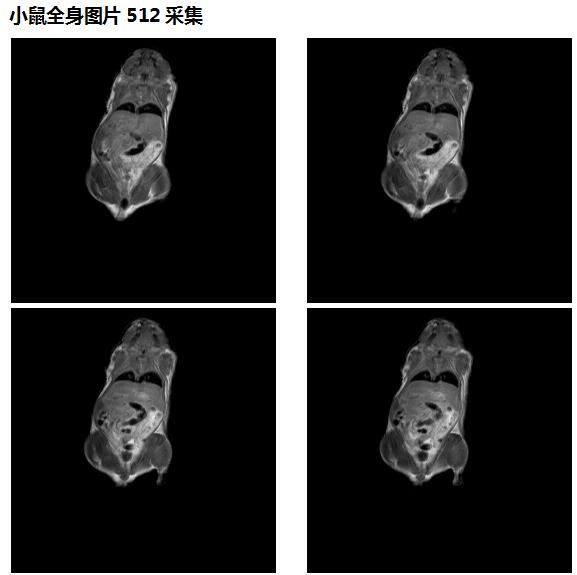

*7、图形分辨率:普通模式 128×128×128 最高分辨率 256×256×128,

14、空间分辨率:普通模式0.15mm 最高模式0.05mm

4、核磁共振成像科研性实验样品观察(小鼠,小动植物体等样品的三维、二维成像实验),小鼠分子影像科研实验研究;

肿瘤鼠图片